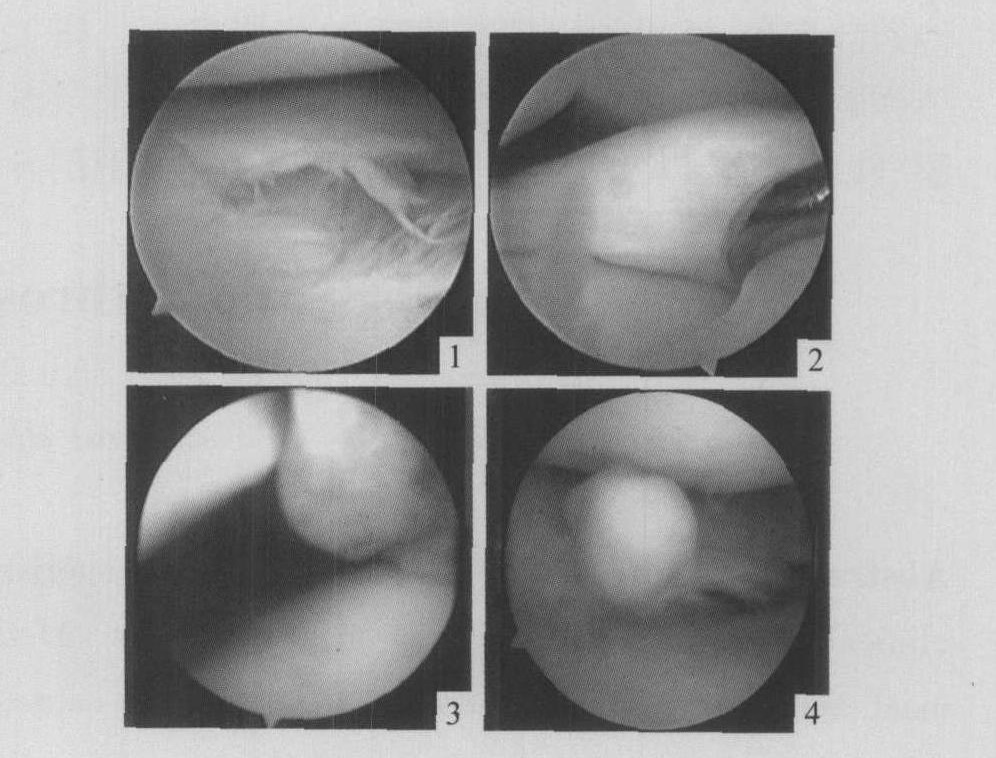

图1 内侧半月板体部水平撕裂合并瓣状撕裂

图2 盘状半月板外形完整、内部存在水平撕裂

图3 髌内侧滑膜皱襞综合征

图4 膝关节内游离体位于外侧间室